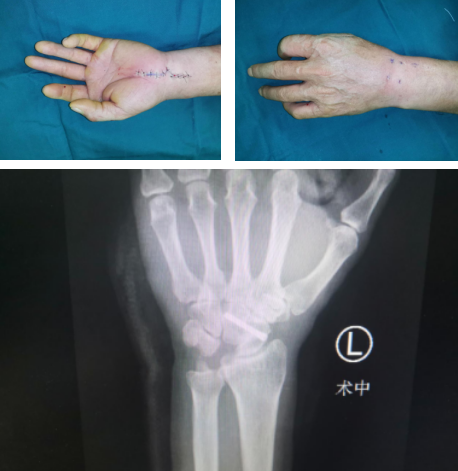

在进行检查之后,滕道练医师团队为孙先生进行了月骨摘除手术,术中在同时在关节镜下清扫滑膜,这个手术对孙先生疼痛的治疗有很好的改善,术后孙先生的疼痛感基本消失。

朱辉主任提醒:在遇到创伤后可能会出现关节疼痛、活动受限等一系列问题,必要时应该来到专业的医院进行检查,避免出现更大的问题和后遗症。